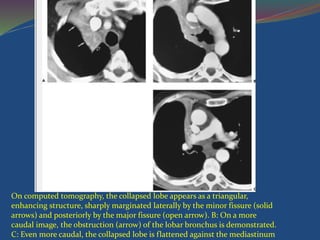

 On CT, the collapsed RUL is seen as a sharply defined

laterally and the major fissure posteriorly

On computed tomography, the collapsed lobe appears as a triangular,

enhancing structure, sharply marginated laterally by the minor fissure (solid

arrows) and posteriorly by the major fissure (open arrow). B: On a more

caudal image, the obstruction (arrow) of the lobar bronchus is demonstrated.

C: Even more caudal, the collapsed lobe is flattened against the mediastinum

 On CT,the collapsed RUL is seen as a sharply defined triangular density bordered by the minor fissure laterally and the major fissure posteriorly

On computed tomography,the collapsed lobe appears as a triangular, enhancing structure, sharply marginated laterally by the minor fissure (solid arrows) and posteriorly by the major fissure (open arrow). B: On a more caudal image, the obstruction (arrow) of the lobar bronchus is demonstrated. C: Even more caudal, the collapsed lobe is flattened against the mediastinum